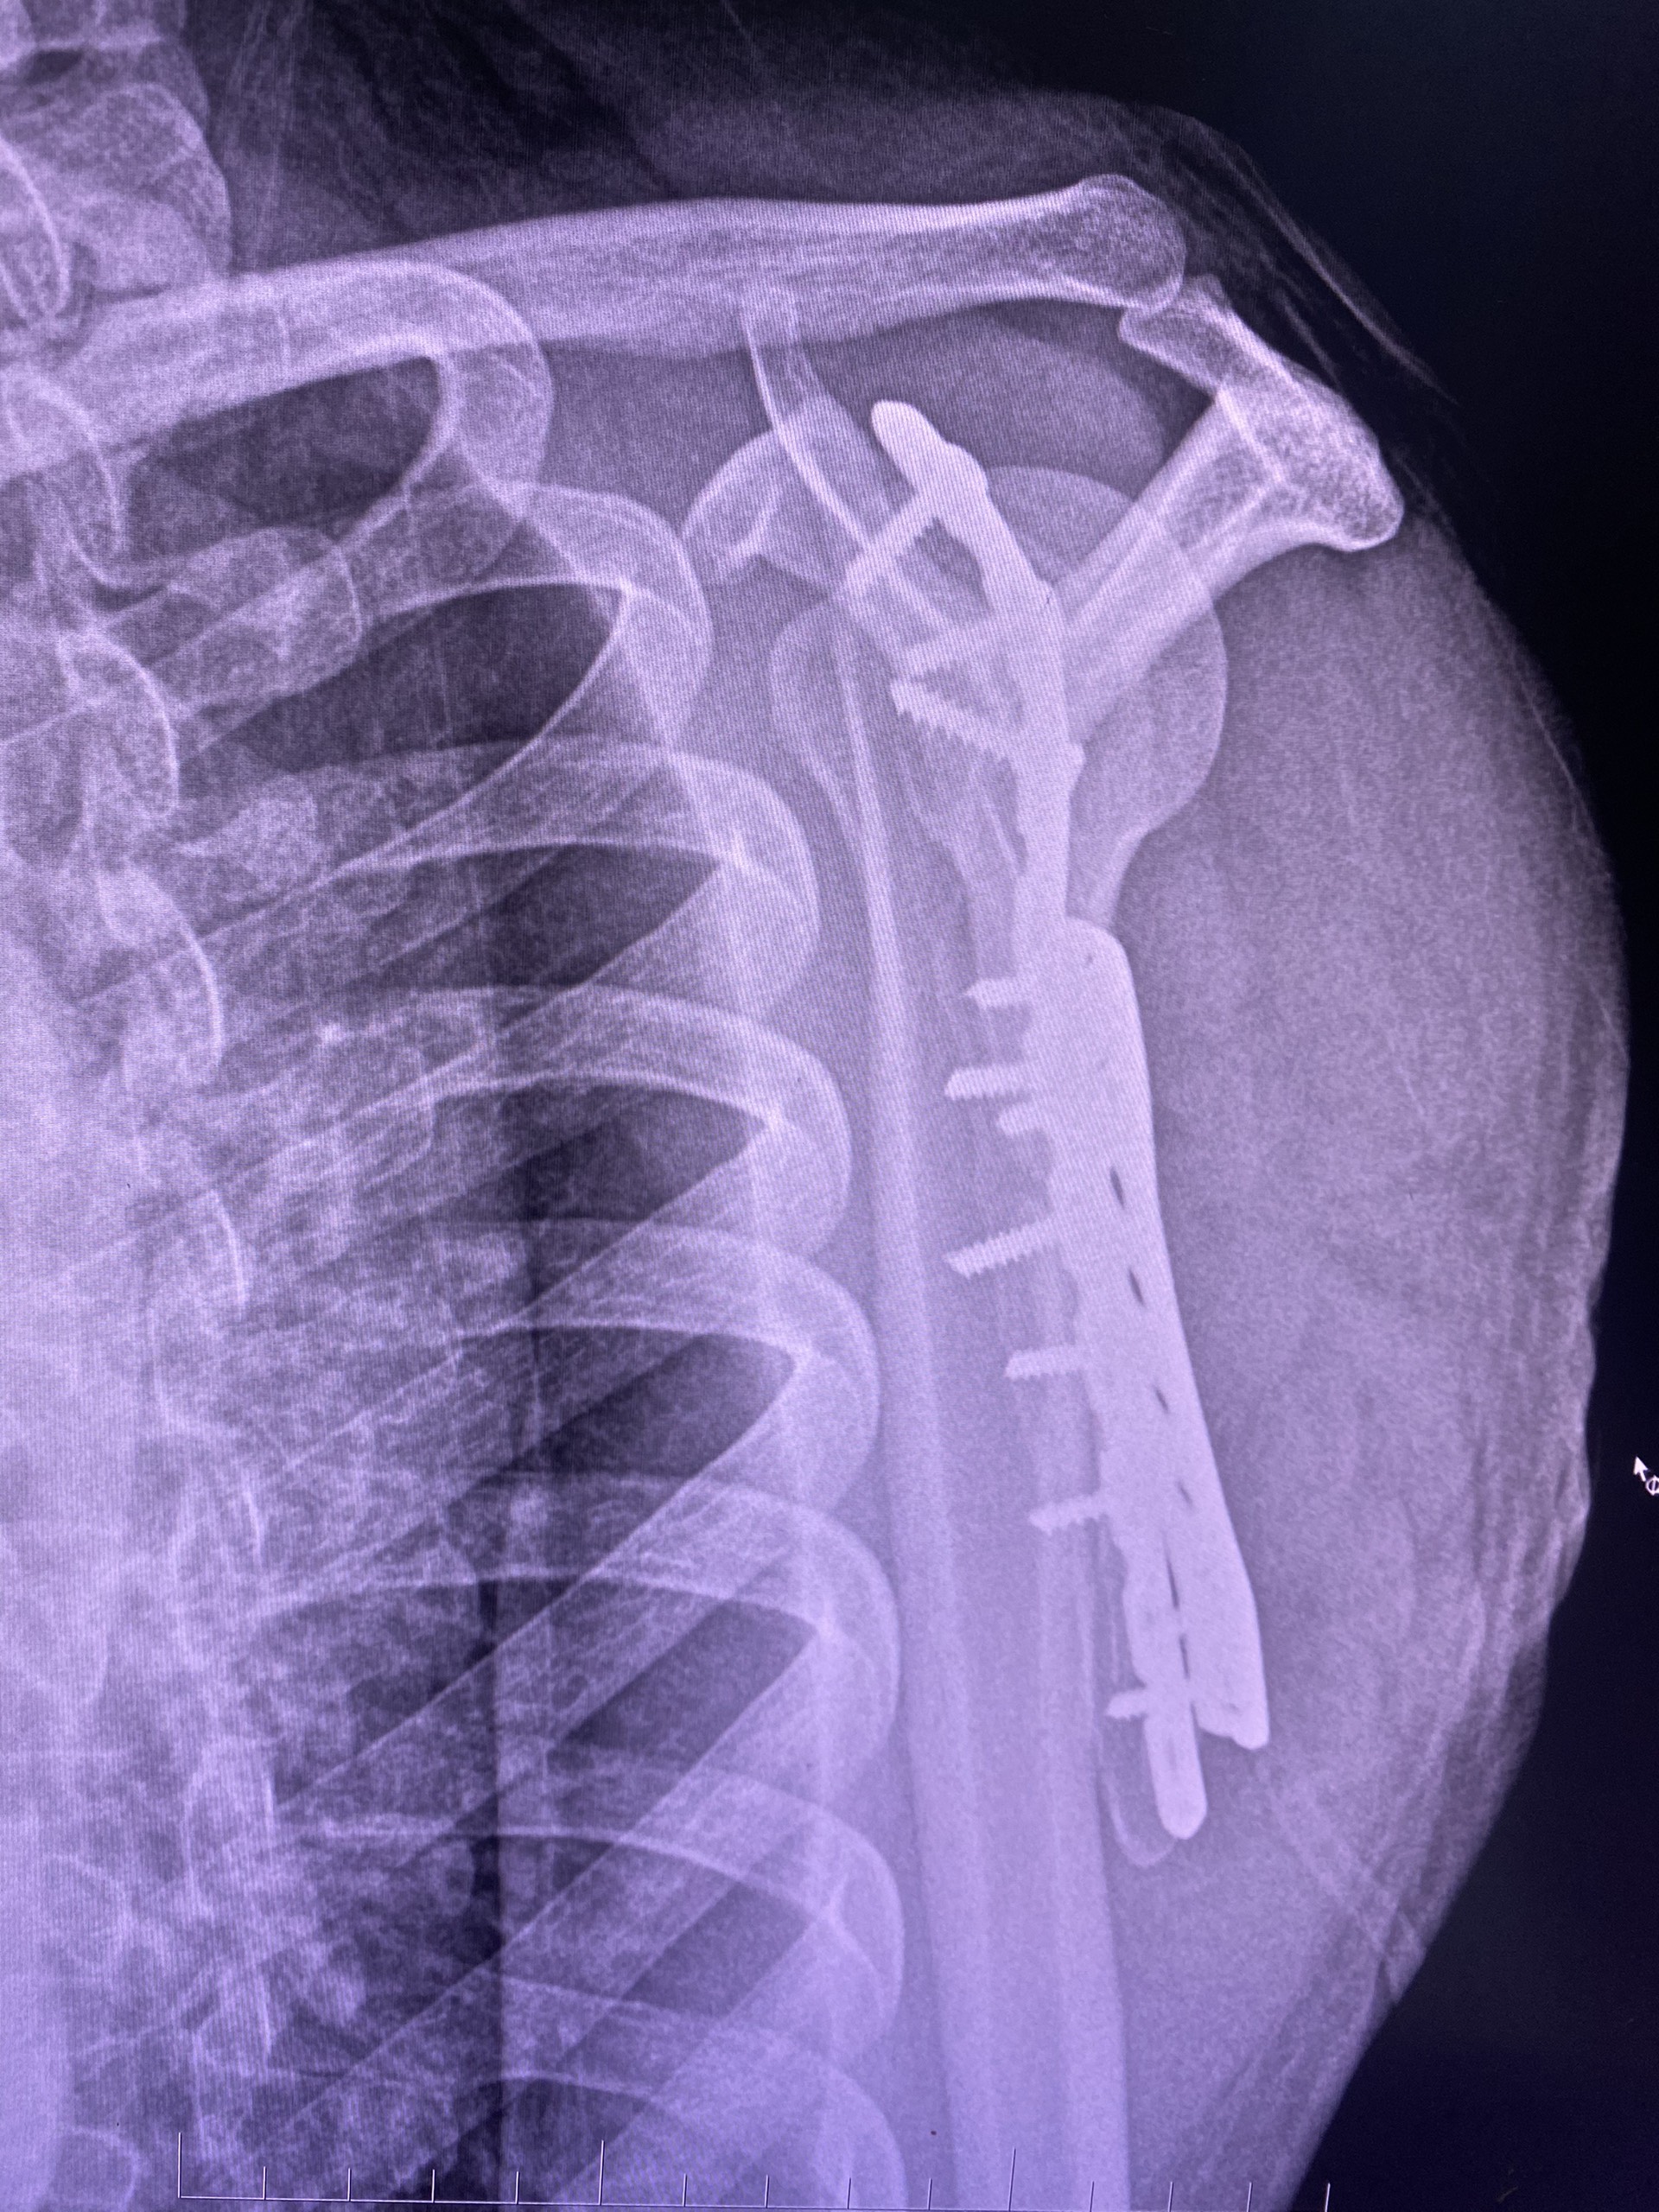

Anh C được kiểm tra kỹ lưỡng các điều kiện đảm bảo và được hội chẩn kíp mổ. Ngày 27/4/2023, người bệnh được tiến hành phẫu thuật, sau hai giờ đồng hồ, kíp mổ với tinh thần hết sức tập trung ghép các mảnh xương vỡ vào đúng vị trí giải phẫu và kết xương bằng 02 nẹp và 10 vít cứng. Ca mổ đã thành công tốt đẹp.

Người bệnh tiếp tục được điều trị, chăm sóc hậu phẫu tại khoa Ngoại Tổng hợp – Chuyên khoa. Năm ngày sau phẫu thuật, tình trạng người bệnh ổn định, vết mổ khô, đỡ đau. Bác sỹ trưởng khoa đã trực tiếp hướng dẫn người bệnh và người nhà về chế độ ăn uống, tập luyện, lịch tái khám. Bệnh nhân được xuất viện vào ngày 05/5/2023.